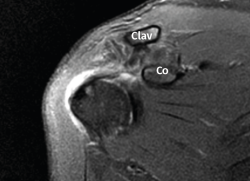

Figura 3. Realizamos la selección del punto en el cuello de la coracoides de forma percutánea bajo visión directa artroscópica. Hombro derecho con la óptica en un abordaje anterolateral. Clav: extremo distal de la clavícula; Co: cuello de la coracoides.

La técnica artroscópica empleada fue la denominada de cerclaje de suspensión cortical coracoclavicular(2). Por encontrarnos más habituados, empleamos la posición de decúbito lateral y los portales de artroscopia posterior, anterolateral y 2 portales anteriores realizados para abordar el espacio subcoracoideo bajo visión directa, según la técnica descrita(5,6,7). En los 6 primeros casos empleamos el dispositivo AC TightRope® (Arthrex, Inc., Naples, Florida). A pesar de su analogía, pero motivado por el cambio de diseño realizado en dicho dispositivo y por el menor orificio requerido, en los 16 restantes casos hemos utilizado el dispositivo AC EndoButton TwinBrigde® (Smith & Nephew, London, England). En los casos con lesiones acompañantes, se emplearon los dispositivos OsteoRaptor 2,3® (Smith & Nephew, London, England) para la reconstrucción de las lesiones de tipo SLAP y el dispositivo TwinFix PK 5,5® (Smith & Nephew, London, England) para el tratamiento de las lesiones de los tendones del manguito rotador. En los últimos 6 casos hemos desestimado el empleo de las guías diseñadas para la implantación de estos dispositivos. Encontramos que su empleo es engorroso, dificulta la selección de los puntos de realización de los túneles óseos y prolonga el tiempo quirúrgico. Optamos por la inserción de las agujas-guía en el extremo clavicular al comienzo de la intervención (Figura 2). En este momento los relieves óseos son fácilmente apreciables. La selección del punto en el cuello de la coracoides se realiza de forma percutánea bajo visión directa (Figura 3). Tras realizar los túneles óseos por taladrado sobre las agujas-guía en la forma habitual, estos se conectan mediante un hilo Vicryl® n.º 2 (Ethicon Endo-Surgery Inc., Cincinnati, Ohio, United States) que hace de pasador final del dispositivo elegido (Figura 4). Si es necesario, se completa la reparación de la fascia trapeciodeltoidea y/o de la cápsula acromioclavicular superior a través del miniabordaje superior asociado.